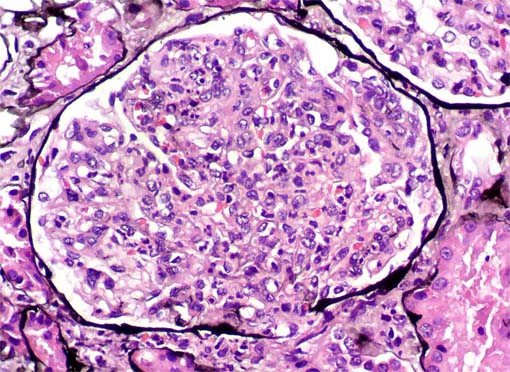

Figura 2.

H&E, X200.